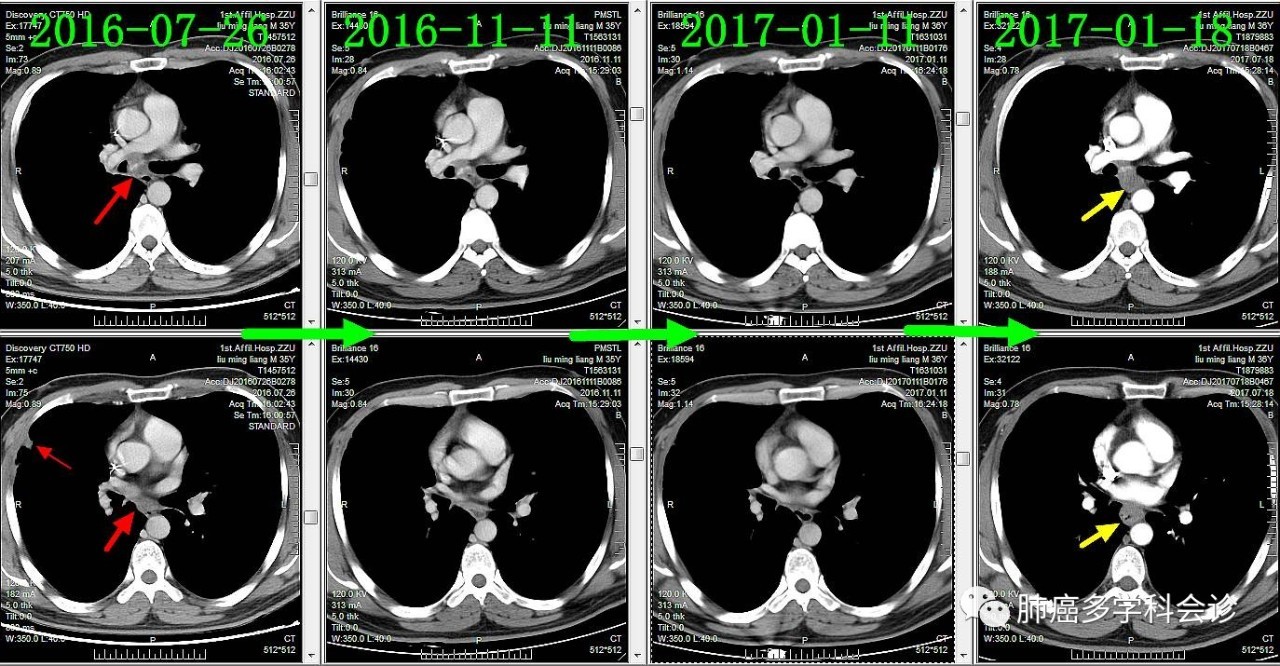

下面着重展示食管转移灶的发展过程。从2016-09-13(完成2个周期化疗)开始,上下两图分别为各时间点CT的上下两层:

食管不是肺癌的常见转移部位,容易被忽视。回顾该患者以往的胸部 CT 可见:在纵隔淋巴和原发灶逐渐退缩过程中,食管转移却逆势发展起来,反映了肿瘤对治疗反应的异质性。